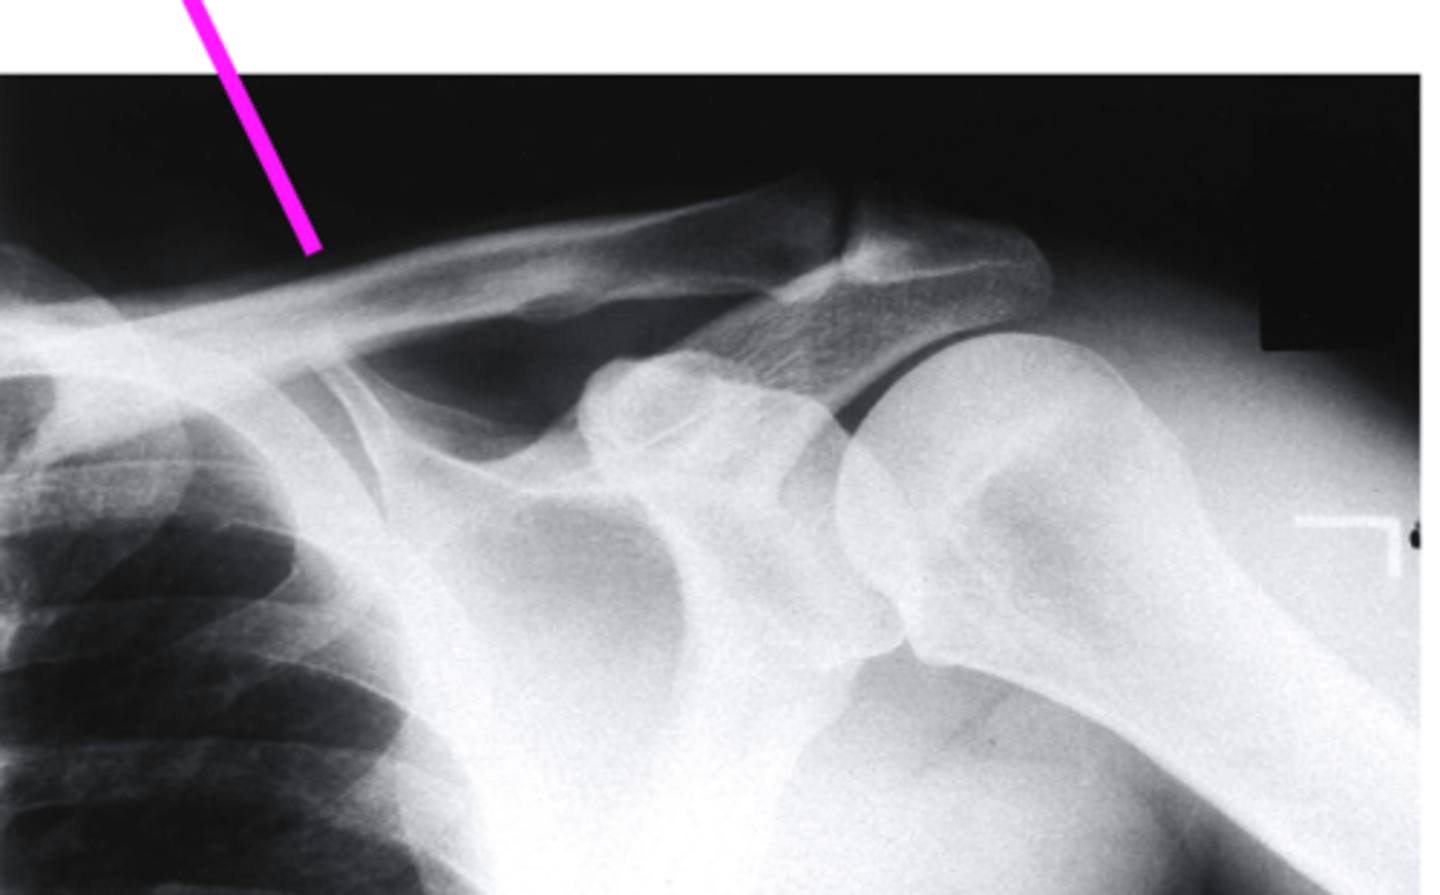

AP + ER

What view is this?

clavicle

what does the pink line point to?

spine of scapula

coracoid process

AC joint

acromion

Humeral Head

Greater Tuberosity

lesser tuberosity

Anatomic Neck of Humerus

Surgical Neck of Humerus

Shaft of Humerus

glenoid fossa

body of scapula

axillary border of scapula

vertebral border of the scapula